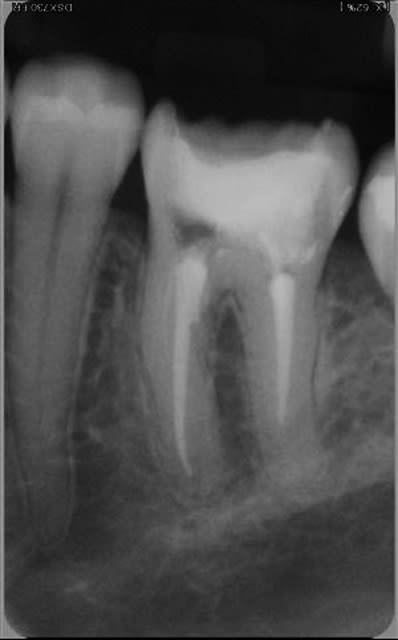

06/02/2009 à 19h22

chacun son truc:j'ai joué quant à moi l'autruche et evité soigneusement les endos jusqu'à aujourd'hui pr croire encore un peu que j'avais progressé

mais qd faut y aller,faut y aller et perdu pr perdu...

une 46:le pronostic?

35:decouverte fortuite sous un si joli inlay or que je l'ai rescellé(adieu CCC...)

et un puff:sniff!(j'essaye pourtant,stephane,j'essaye de les supprimer)